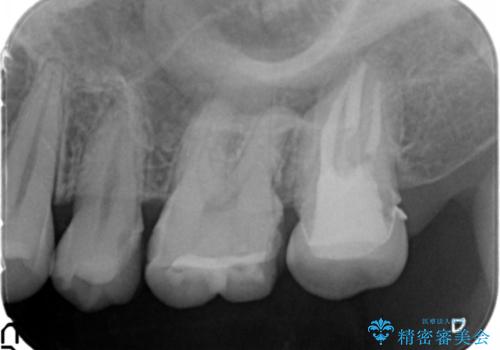

精査したところ、ほとんどの歯が保険内のレジンで充填されており、咬み合わせも悪く咬合していない歯もありました。

虫歯をしっかりと治療したのち、オールセラミッククラウンによる補綴治療を行いました。

下顎の埋伏していた親知らずも抜去しました。